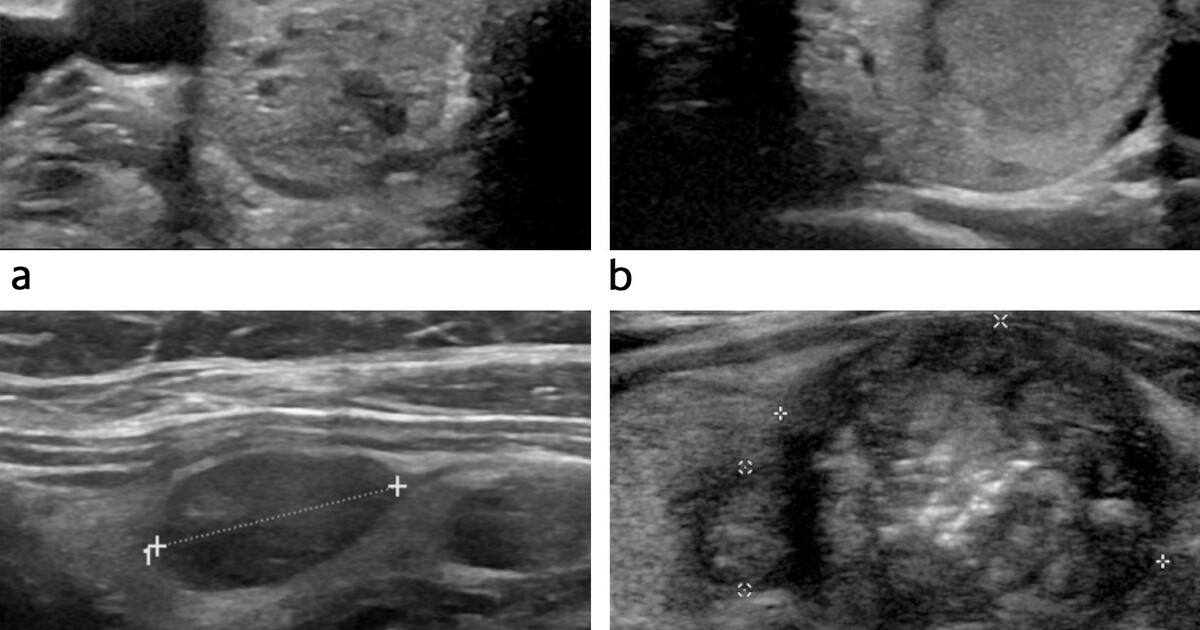

Thyroid nodules review. Up to 50% of people have thyroid nodules, which are mostly benign (90–95%) but need to be evaluated to rule out malignancy (5–10%). History, examination, TSH blood test, and thyroid ultrasound are the first stages; suspicious ultrasound characteristics (solid, hypoechoic, macrocalcifications) may trigger a Fine Needle Aspiration (FNA) biopsy, which is the gold standard for diagnosis and determines if surgery or close observation is required.

Diagnosing thyroid nodules typically involves a combination of a physical exam, blood tests to assess thyroid function, ultrasound imaging, and sometimes a fine-needle biopsy to determine if the nodule is benign or malignant.